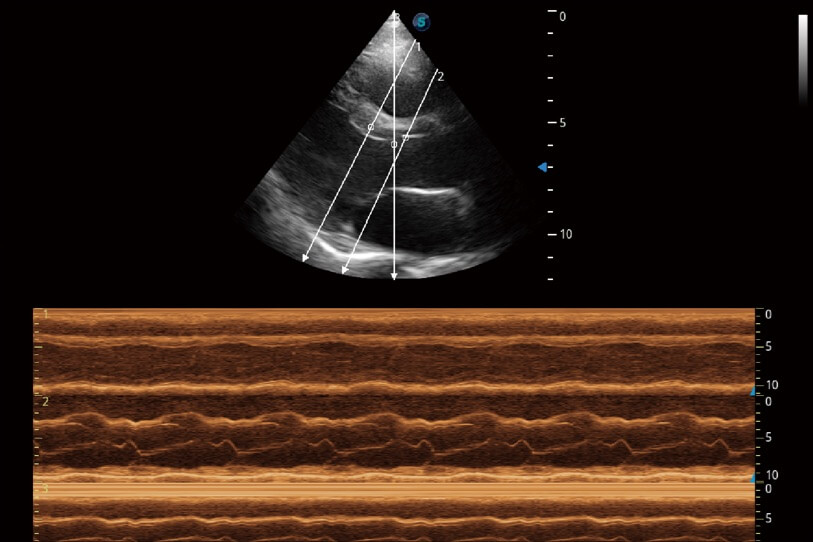

通過(guò)360度任意調(diào)節(jié)3條M型取樣線(xiàn),在同一心動(dòng)周期上觀(guān)察心臟不同位置的運(yùn)動(dòng)曲線(xiàn),得到準(zhǔn)確的心功能測(cè)量數(shù)據(jù),有效評(píng)估心肌運(yùn)動(dòng)及左心室功能。